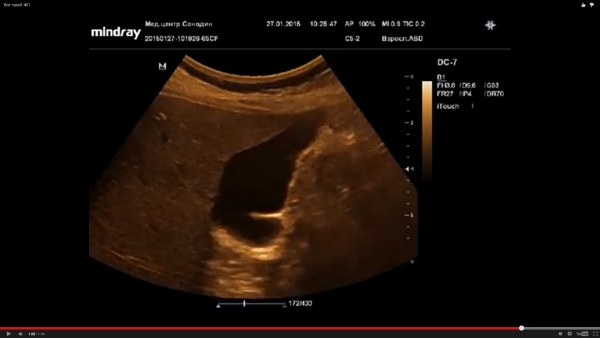

По поводу ролика Дмитрия - я бы написал здесь как раз этот пресловутый хронический холецистит, стенки фиброзно изменены.. Ну и перегиб, понятно.

Что касается перегибов, то я почти никогда не пользуюсь этим термином, т.к почти всегда это не перегиб, а обычная изогнутость, а если это так то и писать

в заключении -"Перегиб ЖП" не нужно!

Форма ЖП то же большого клинического значения не имеет, поэтому я ее описываю, но в заключение не выношу!

Перетяжки в 95% случаях не перетяжки, а стенка изогнутого пузыря.